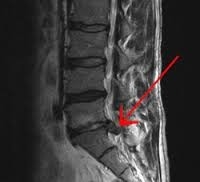

De diagnose wordt vermoed op basis van het klachtenpatroon. Het neurologisch onderzoek laat soms tekenen zien van een zenuwwortel-beknelling (pijn tijdens het oprekken van de zenuw of afwijkende reflexen aan de benen), maar kan ook volledig normaal zijn. Een MRI scan van de onderrug kan aantonen of er daadwerkelijk sprake is van een hernia.